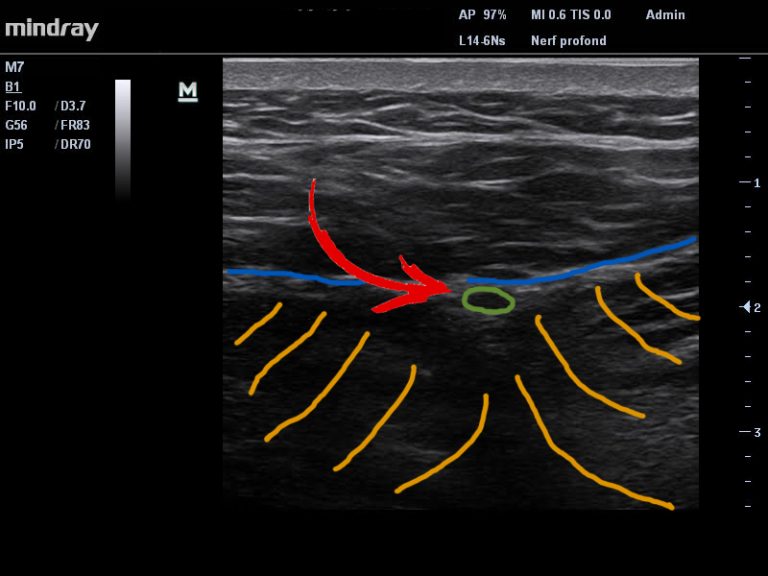

L’examen échographique comparatif nous permet de mettre en évidence la présence d’un oedème intra-neural au niveau de l’un des ces NCS juste en amont du point où ce nerf quitte la loge musculaire du dos pour se diriger vers la région sous cutanée fessière en passant au travers du fascia thoraco-lombaire  FTL ( Figure 2 et Video 1).

Figure 2. Présence d’un oedème intra-neural (rond vert) au niveau de l’un des NCS. Fascia Thoraco-Lombaire (ligne bleue). Muscles extenseurs (lignes jaunes).